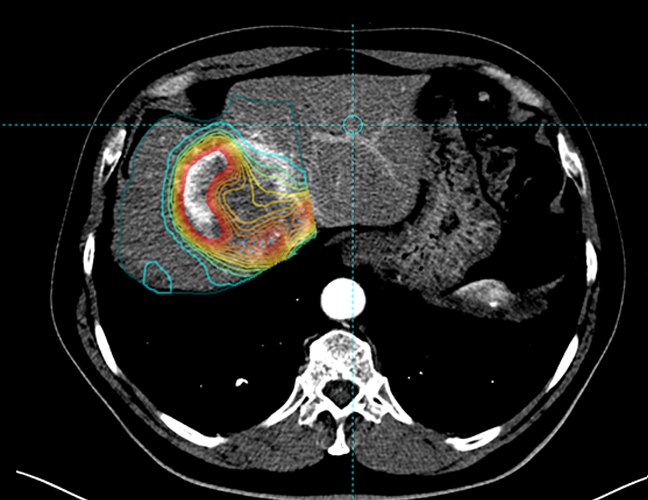

Simplicit90Y™ provides the capability to visualise prospective dose distribution and assess the absorbed dose delivered to the tumour and normal tissue.

By allowing for pre and post-treatment dosimetry, this software can help determine the effectiveness of a

patient’s 90Y SIRT with confidence.

View absorbed dose distribution with isodose

contour line display

Show heterogeneity of absorbed dose distribution in

critical structures, and assess tumour coverage